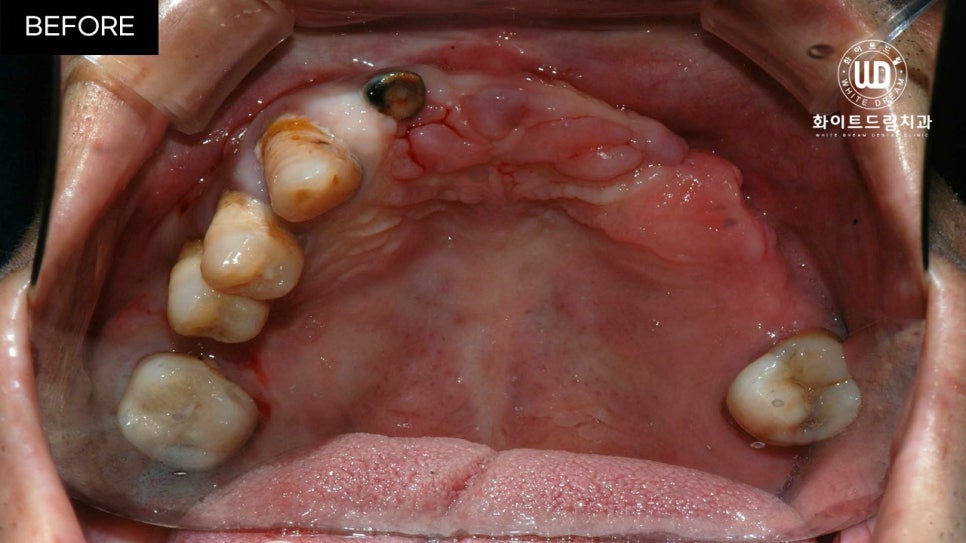

임플란트 식립 전 상, 하악 모습입니다.

육안으로 보이실지 모르겠으나 잔존한 치아 주위염이 심한 상태셨는데요. 뿐만 아니라 치아 파절과 함께 영구치의 뿌리 대부분이 손상되어 있는 상태였습니다.

이미 발치되어 있는 쪽은 치아가 소실된지 오랜 시간이 지나 잇몸뼈가 부족한 상태였고, 현 상태로는 픽스쳐를 식립할 수 없어 전체 발치 후 상악 양측 구치부 상악동 거상술 및 전체 치조골 이식을 동반한 전체 임플란트 식립을 진행하기로 했습니다.